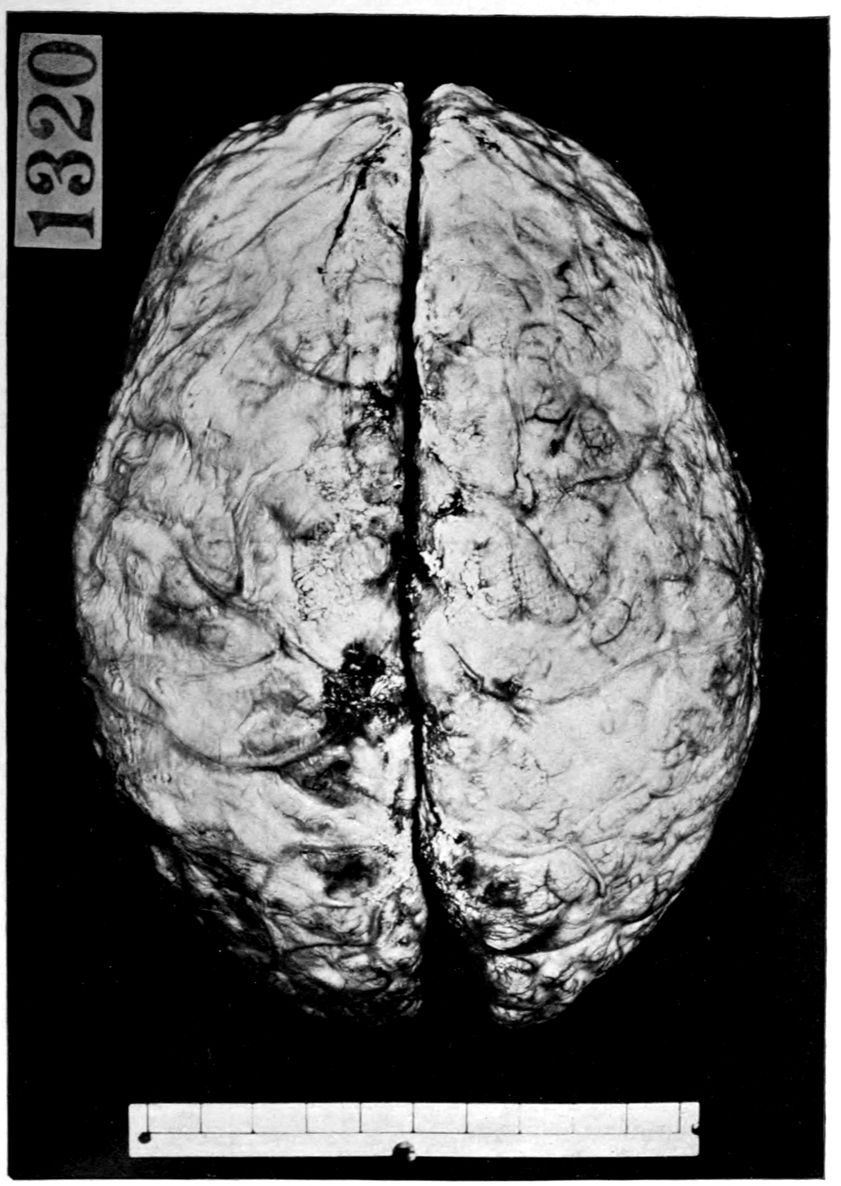

The calvarium was dense and the dura mater thick and adherent. There was a chronic leptomeningitis, which, however, was rather unusual in being most marked in the posterior cisterna and along the sulci of the cerebellar hemispheres. There was a general cerebral sclerosis, with a question of atrophy of the superior temporal gyri (suggesting the so-called Lissauer’s paresis). There was a marked cerebellar sclerosis with a consequent sclerosis (grossly palpable) of the commissural fibres of the pons. There was a generalized slight spinal sclerosis. As a fair sample of the variety of head findings in paretic neurosyphilis, the details of the head examination are presented.

39Crown bald, with a slight fuzzy growth of short hairs. Scalp slightly adherent to calvarium; latter of usual thickness but denser than normal. Dura adherent to calvarium in region of vertex; dura not remarkable. Sinuses normal. Arachnoid villi moderately developed. Pia mater a trifle thickened and rather evenly throughout the cerebral portion. Linear sulcal markings are remarkable for their absence. The wall of the cerebellomedullary cisterna is thick and opaque. The most prominent pial thickenings are over the cerebellum. These are linear or may show feathery out-growths and are seated over the sulci, particularly in the neighborhood of the fissure and about the great cerebellar notch. They correspond fairly well with the focal variation in consistence of underlying tissues noted below.

Brain weight, 1265 grams. Consistence somewhat increased throughout and somewhat evenly increased. The prefrontal region shows the maximal increase of consistence but the remainder of the frontal region and corresponding occipital region are much firmer than normal. The two superior temporal gyri appear to be firmer than adjacent gyri and are possibly slightly diminished in superficial diameter. The hippocampal gyri are fairly firm. The substance on section is a trifle more moist than normal. The gray and white matter cut quite evenly. Diminution in depth of gray matter, if existent, could not be demonstrated. The ventricles show a moderate sanding throughout, best marked in the fourth ventricle. The basal ganglia are not remarkable except for the development of numerous dilated perivascular spaces about the lenticulostriate vessels. The pons is atrophic, but more so on the right side. The pons, like the prefrontal cortex, shows on section a distinct increase of consistence immediately beneath the pia mater. The white bands of the pons on section are distinctly firmer than the intervening substance. The olives are of equal consistence. Weight of cerebellum, pons, and medulla, 155 grams. The cerebellum shows an obvious atrophic and gliotic process of a symmetrical character. The superior surface, including both vermis and hemispheres, shows a consistence above normal and general reduction of the depth measured from the white matter. The reduction in depth gives rise to a visible depression as compared with tissue posterior to the postclival sulci. The lobus cacuminis, though slightly raised from the surrounding lobes, is equally firm, if not firmer. The superior and inferior surfaces show practically an equal increase of consistence. The dentate nuclei are not especially increased in consistence. The flocculi are reduced in size about one-third.

Parenchymatous losses have led to Atrophy and Sclerosis, of very varying extent in different parts of the encephalon. The atrophy is characteristic in paretic neurosyphilis, but by no means constant. Numerous cases have come to autopsy without clearly defined gross atrophy. Sclerosis is also characteristic and even more frequent than atrophy, doubtless because sclerosis represents an earlier phase of a process eventuating in gross atrophy.